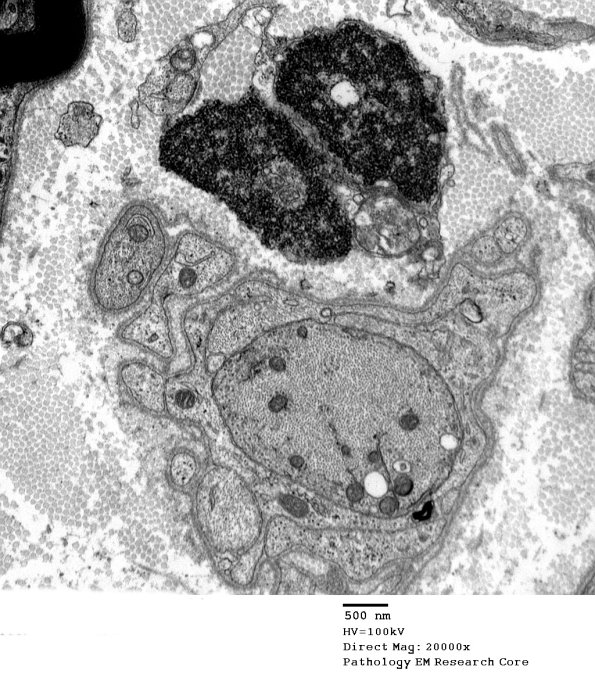

5B6,7 Demyelinated axons without remyelination. Notice there is no myelin debris in the surrounding Schwann cell. (electron micrograph)